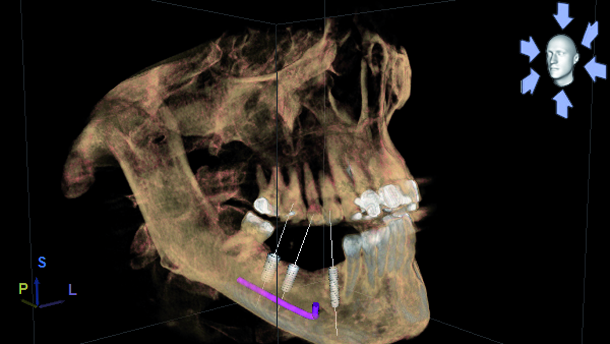

Sirona’s GALILEOS scan travels around the patients’ head in a single revolution that takes 14 seconds to complete the capture of the maxillofacial anatomy and a full volume of data is reconstructed and becomes available to assess within minutes. My patient and I reviewed the 3-D images together on a large computer monitor in my conference room. I was able to place three virtual implants into the residual bone avoiding the IAN, mental foramen and lingual concavity. Patient could clearly visualise this procedure being performed in his jaw. In this case the bone appeared adequate to receive three endosseous implants that could be restored with a 4-unit fixed bridge (Figs. 4–7). So to recap, this patient was reluctant to be treated with conventional flapped implant surgery and declined additional bone grafting to improve any bone volume, but was a candidate for flapless or minimally flapped guided implant surgery which gave him the confidence to accept treatment based upon our initial consultation and treatment plan which was developed during this visit. This first step is essential to gain the patient’s trust and gain acceptance to the treatment plan at his initial visit as he would not return to us if he wasn’t convinced that I could perform his treatment as I described and under local anesthesia and without further bone grafting.

The Sirona system is the only complete system that doesn’t require a third party software or manufacturer to create their surgical guides. Figures 8–10 show the virtual implants placed into the area of tooth #28, 30 and 31. Please note the measurement taken buccal-lingually at the #28 site and the anatomical limitations dictated by the lingual concavities present at the #30 and #31 sites. Some compromises were necessary to ensure safe, predictable and long lasting success of our implants. They were dictated by the anatomical bone limitations present and the patients’ refusal for any additional bone grafting.

The surgical visit was scheduled and I placed the patient on Amoxicillin 500 mg to be taken two days prior to his implant surgery and continued until the prescription was completed. Patient presented on 9 January 2014 and was anxious but ready to proceed with his implant placement. An inferior alveolar block with local anaesthesia was given and was effective to produce profound anaesthesia during our treatment. Osteotomy preparations were completed in a timely manner and three Nobel Active (Nobel Biocare) implants were installed as planned.

The #31 site was completed with a flapless approach but I wanted to examine the #28 site to be certain that my preparation was indeed perfectly accomplished. The #30 site required a flap to move the keratinised tissue from the lingual to the buccal. So the #28 and 30 implants required mini flaps and were second staged, which later required uncovering to access the platform during the impression procedure. The surgery went well and the patient tolerated the 1 hour visit without incidence. He commented post-operatively that he experienced no pain and did not realise how uncomplicated this treatment could be. He was able to resume all normal activities immediately without any restrictions. My years of experience have given me the necessary skills to manage these patients and their surgeries in a quick, minimally traumatic approach resulting in less post-operative problems and faster healing times versus conventional wide flap implant surgeries. Note how the plan and the actual match up well in my periapical X-rays (Fig. 11).